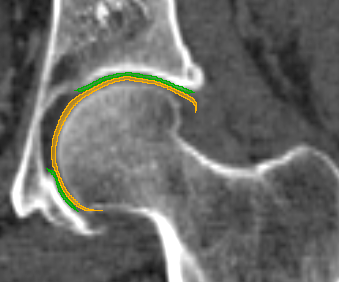

We have qualitatively verified that the articulating surfaces in all the ten HJs are detected correctly regardless of their anatomical variance using visual inspection of overlays as shown in Fig. 4. As desired, we observe a high degree of congruence between the opposing joint surfaces, meaning no gaps or overlaps in the cartilage-cartilage interface. Moreover, we observe a smooth transition towards the bone geometries as expected from the correct anatomy. The parameter values used to generate the cartilage from Fig. 5(a). The free parameters are the neighbourhood-size used to estimate the curvature of the bone (𝒩𝒩\mathcal{N}); the minimum and maximum curvature in the cartilage region (κmin,κmaxsubscript𝜅subscript𝜅\kappa_{\min},\kappa_{\max}; Eq. (2)); the distance parameter in mm𝑚𝑚mm (δ𝛿\delta; Eq. 1); and the number of times the outer boundary should be trimmed (Ntrimsubscript𝑁𝑡𝑟𝑖𝑚N_{trim}). Here, the curvature based parameters (𝒩,κmin,κmax)\mathcal{N},\kappa_{\min},\kappa_{\max}) are only used for the femur. See supplementary material for more visual comparisons.

(b) CT scan overlay.

Figure 4: The von Mises stress patterns ((a)) and the generated cartilage imposed on the CT scan from which the bone was extracted ((b)). Notice the high level of congruence in the cartilage-bone interfaces and cartilage-cartilage interface.